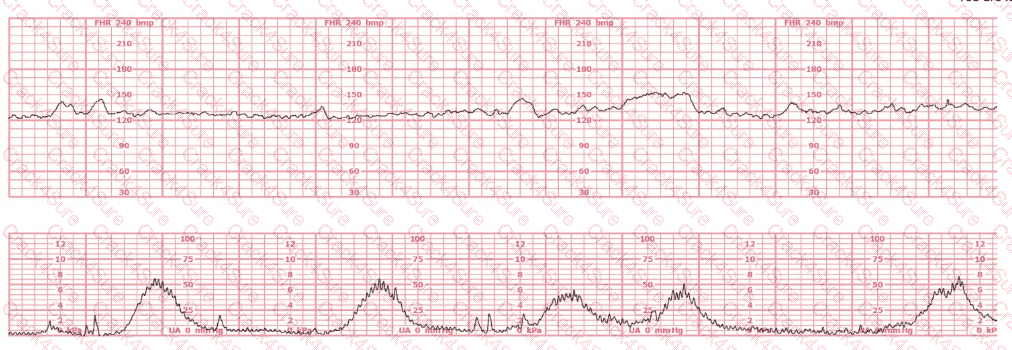

A woman (G1, P0) at 41-weeks gestation presents to OB triage to rule out labor. Her cervical exam is 1 cm/50%/-2. Membranes are intact. She would like to go home if not in labor. Based on this tracing, which represents the last two hours, the best approach is: